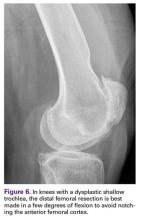

Notching the anterior femoral cortex when in-between femoral sizes or when there is a preexisting dysplastic or shallow trochlea (Figure 6)

Figure 6.

can be avoided by making the distal femoral resection in an extra 3° of flexion. In most TKA systems, the prosthetic trochlear flange diverges 3° or 4° away from the posterior femoral condyles. If the distal femoral resection is made in an extra 3° of flexion, the femoral component utilized can be anatomically sized off the patient’s posterior femoral condyles and the diverging trochlear flange will avoid notching the anterior femoral cortex while providing increased surface contact with the trochlear bone, enhancing prosthetic fixation. The only potential adverse effects of increased femoral component flexion would occur in a system that does not allow hyperextension of the femoral/tibial articulation without loss of articular contact or in a posterior-stabilized articulation where there could be post impingement in hyperextension. Total knee systems vary in the amount of hyperextension that can be tolerated.